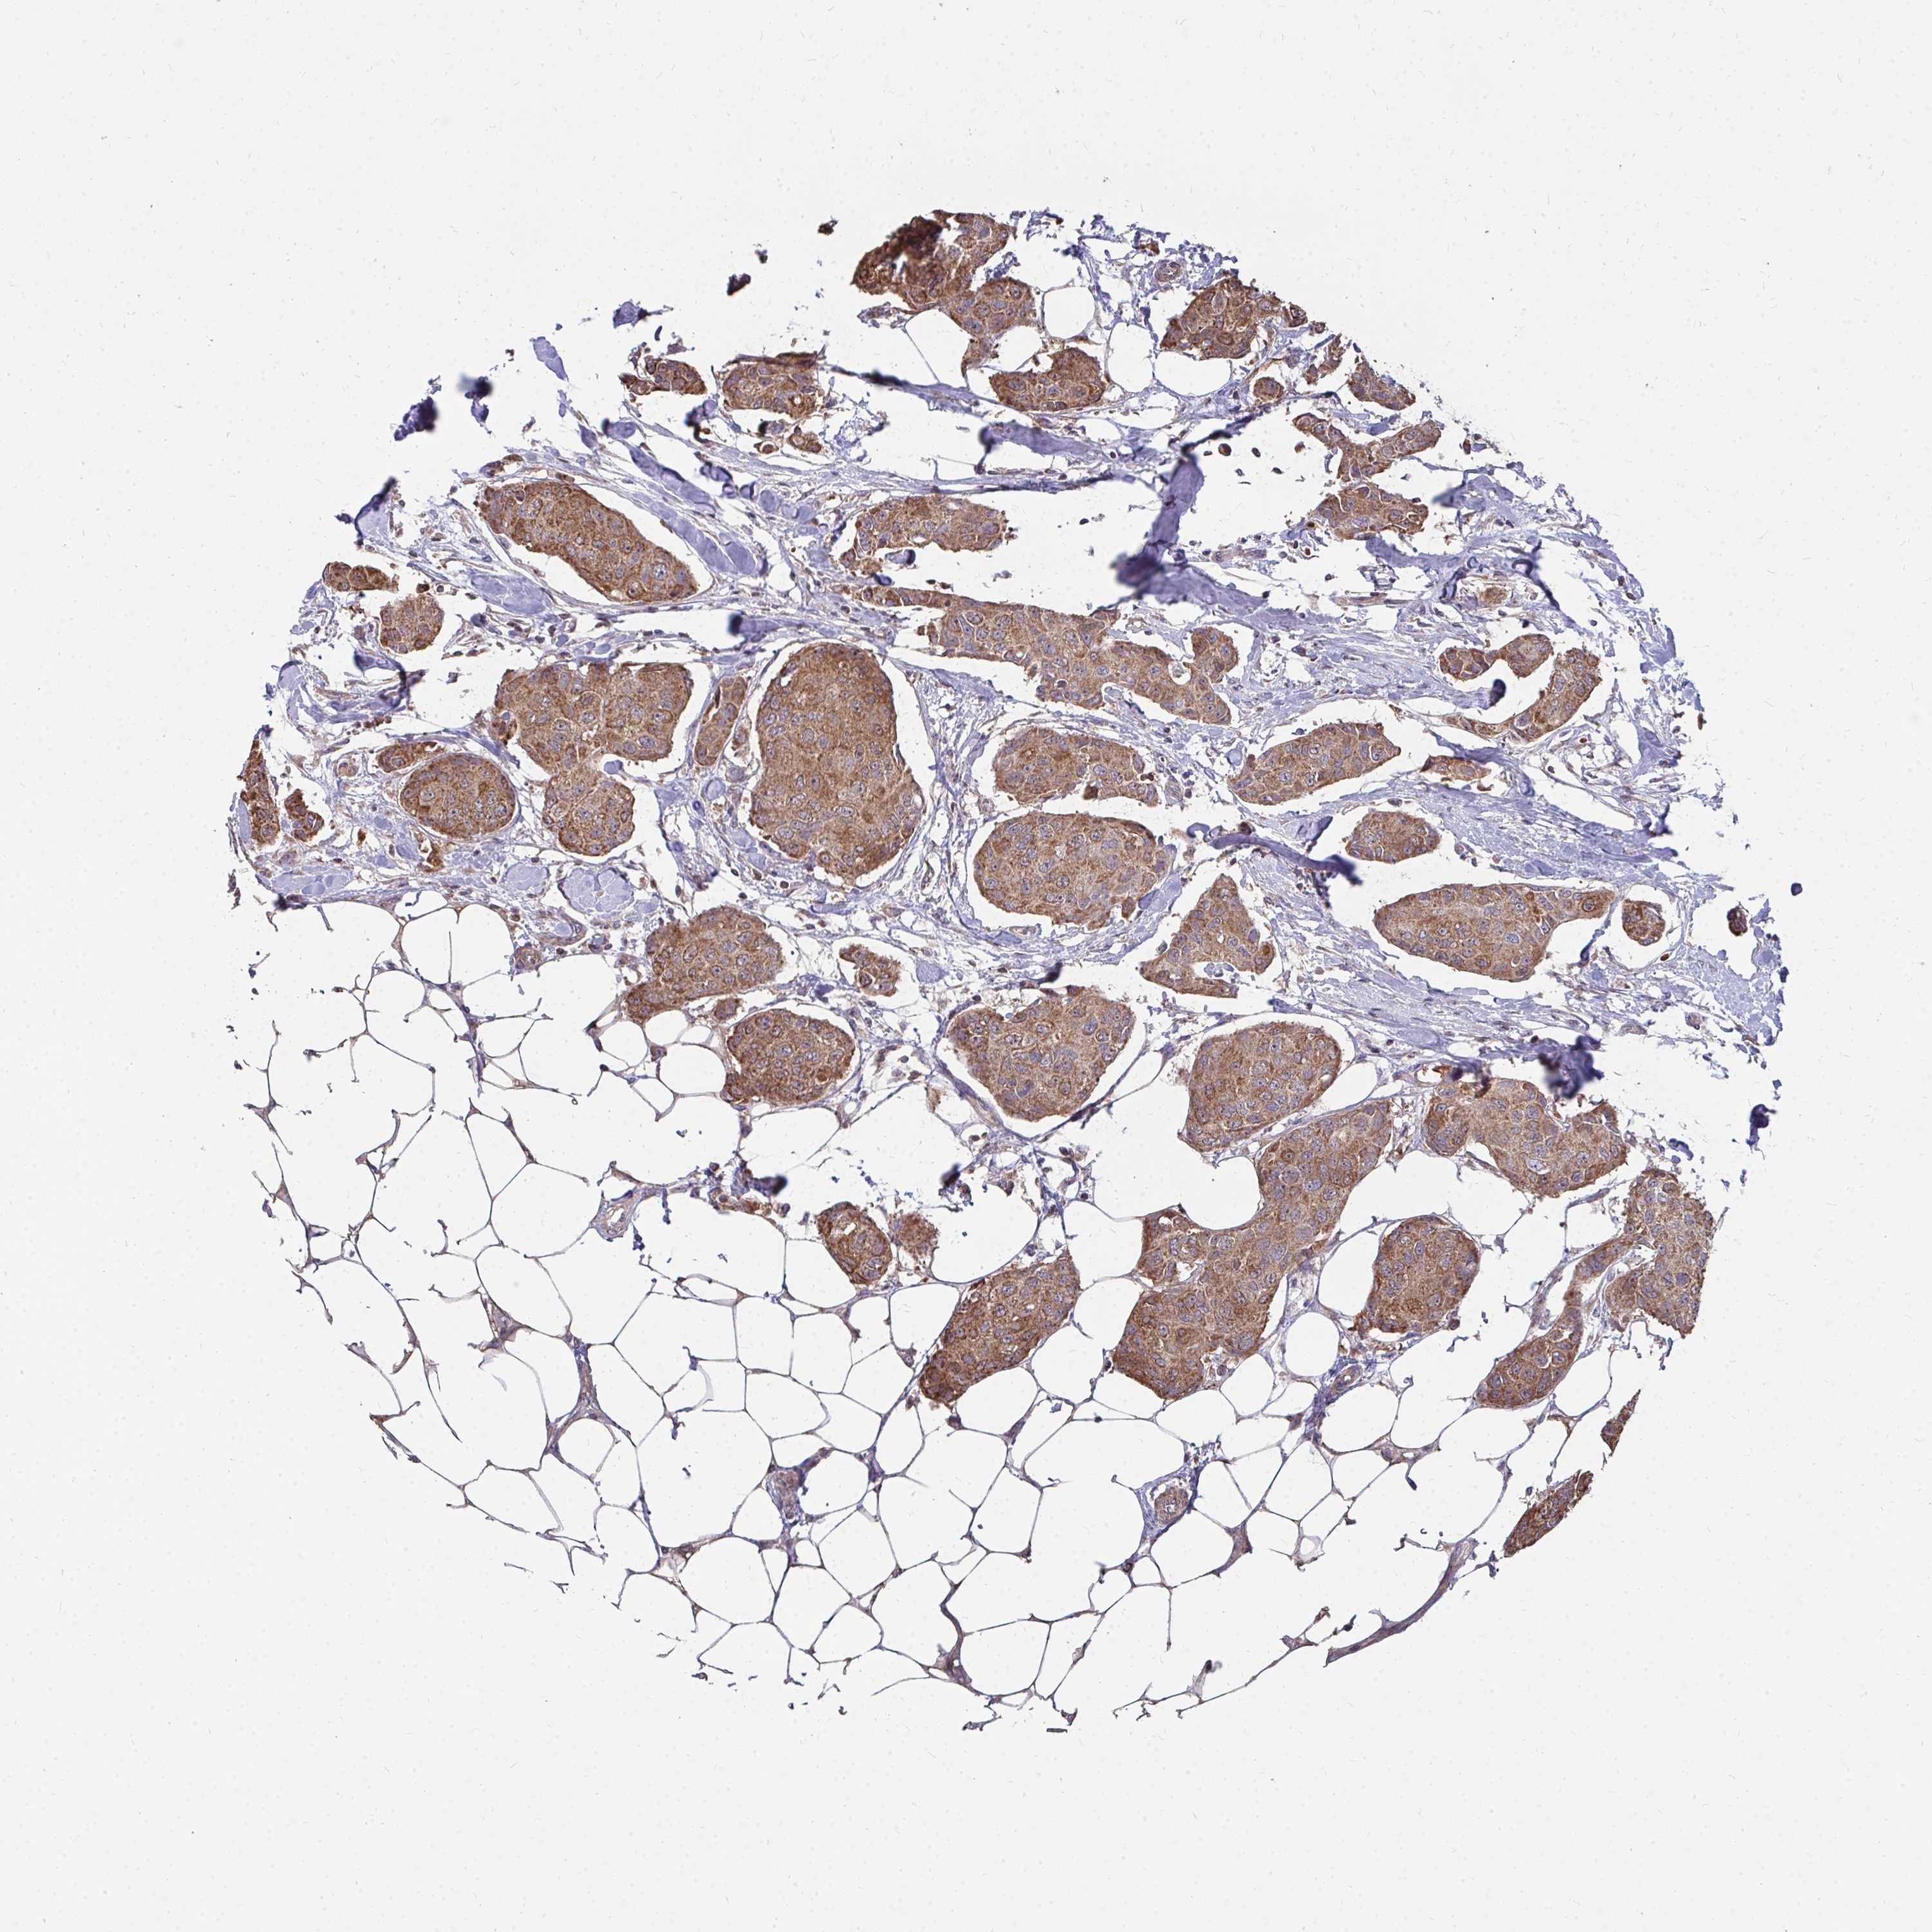

CANCER BREAST CANCER Show tissue menu

Breast cancer

Human cancer